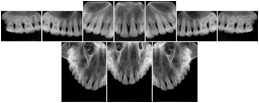

Intra-oral radiography typically involves acquisition of multiple images of various parts of the dentition. Many digital radiographic systems offer customized templates that are used for displaying the images in a study on the screen. These templates may also be referred to as mounts or view sets. The Structured Display Object represents a standard method of encoding and exchanging the layout and intended display of Structured Displays. A structured display object created in this manner could be stored with a study and exchanged with images to allow for complete reproduction of the original exam.

In most standard cases, images are oriented in structured layouts. These structured displays are useful to be shared between providers for reference purposes.

Table OO.1.1-1 shows structured display standard templates, where Viewset ID is based on the Japanese Society for Oral and Maxillofacial Radiology (JSOMR) classification provided by JIRA (Japan Medical Imaging and Radiological Systems Industries Association, www.jira-net.or.jp). Expected or typical teeth to be imaged location, region and designation codes are based on ISO 3950-2010, Dentistry - Designation system for teeth and areas of the oral cavity. For all the hanging protocols listed in OO.1.1-1, the value to use for Hanging Protocol Creator (0072,0008) is "JSOMR" and the value to use for Hanging Protocol Name (0072,0002) does not include "JSOMR" (e.g., "DL-S001A", not "JSOMR DL-S001A").